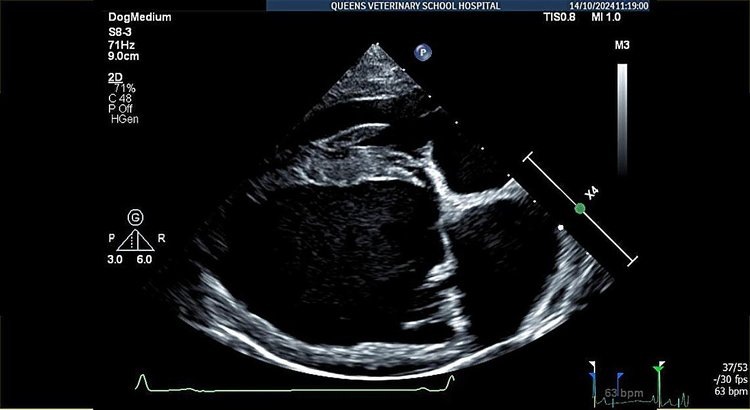

Снимки сканирования сердца собаки с заболеванием митрального клапана, показывающие толстый и протекающий клапан. Автор фото: Хосе Ново Матос.